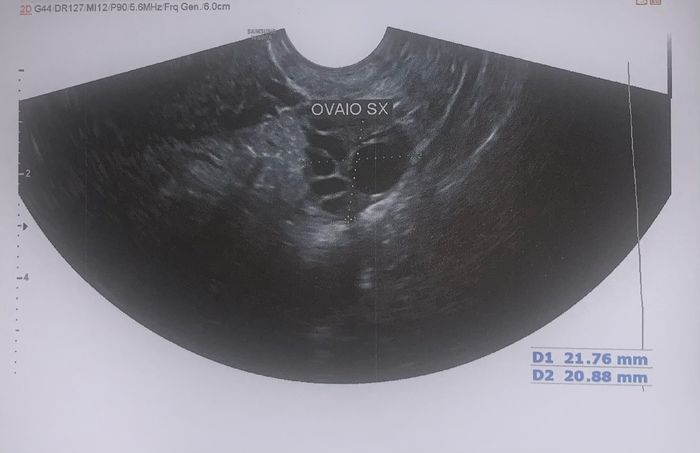

Mi aveva rincuorato la visita che feci dal mio ginecologo venerdì, il quale mi disse di aver visto un follicolo bello grande a sx 14pm test ovulazione negativo 2

Eccolo qua. Lo avevo già postato. E mi disse che avrei ovulato a 7 giorni. Questi 7 giorni saranno trascorsi domani. Ma ancora non ho avuto neanche il picco e senza picco segnalato dubito possa ovulare. C’è da dire inoltre che scorso mese (ho iniziato scorso mese) ho avuto il picco il 18/04.14pm test ovulazione negativo 3Anche se non riesco a capire se quel 40 come valore andasse bene. Tuttavia ero al 21 pm 😕, perciò una parte di me sta solo sperando di ovulare più tardi. C’è da dire inoltre che come ultima mestruazione di riferimento avevo messo il 29/03 ovvero il giorno in cui mi è venuta la mestruazione post beta negative. Che, in fatto tecnico, non so neanche se era da considerarsi come ultima mestruazione oppure no. Così fosse ho ovulato, stando alle foto al 21pm.Però non riesco a capacitarmi anche di quanto mi disse il medico. Anche vero che stamattina forse non era il momento migliore per fare un test?! Però insomma… se la concentrazione di LH è alta secondo me lo rileva e basta sempre. Ma voglio illudermi che al mattino presto potrebbe essere falsato il risultato. Secondo le vostre esperienze può succedere che da linee leggere poi tutto di botto si sono positivizzati? Non sapete quanto ci sto impazzendo (ma lo potete capire) e quanto sia dispiaciuta, depressa, abbattuta.L’unica cosa che desideravo più al mondo mi è stata strappata dal cuore.Vorrei continuare ad essere ottimista 🤞🏻.